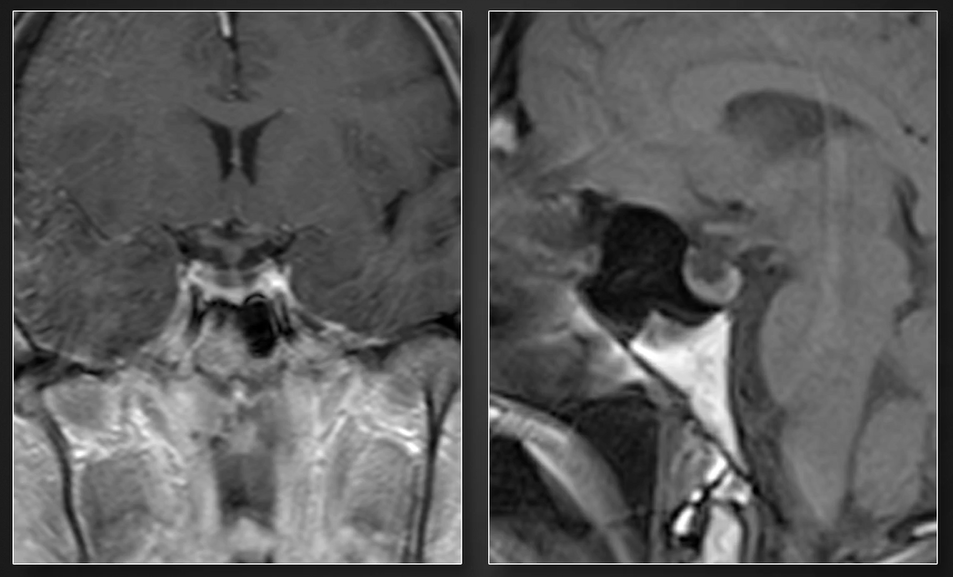

術(shù)前MRI

- 文章標(biāo)題:經(jīng)終板入路切除三腦室腫瘤